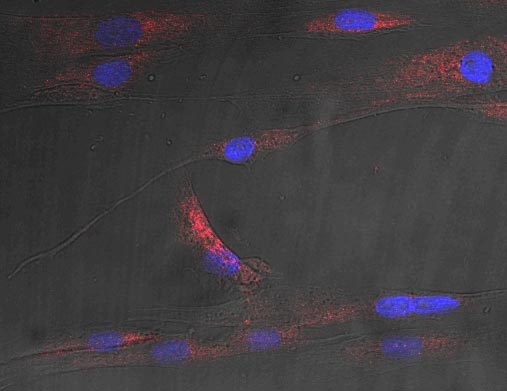

这些信号被称为神经酰胺,在短期内可能有保护作用,因为它们是旨在减少细胞内压力的机制的一部分。但是在代谢性疾病中,也就是长期的情况下,这些信号可能会杀死细胞,使症状更加严重,并使疾病恶化。

长期以来,人们知道血液中的脂肪增加会损害组织和器官,促成心血管和代谢疾病的发展,包括2型糖尿病。这种情况可能是由肥胖引起的,自1975年以来,全世界的肥胖率已经增加了近两倍。2016年,有超过6.5亿18岁及以上的成年人患有肥胖症。